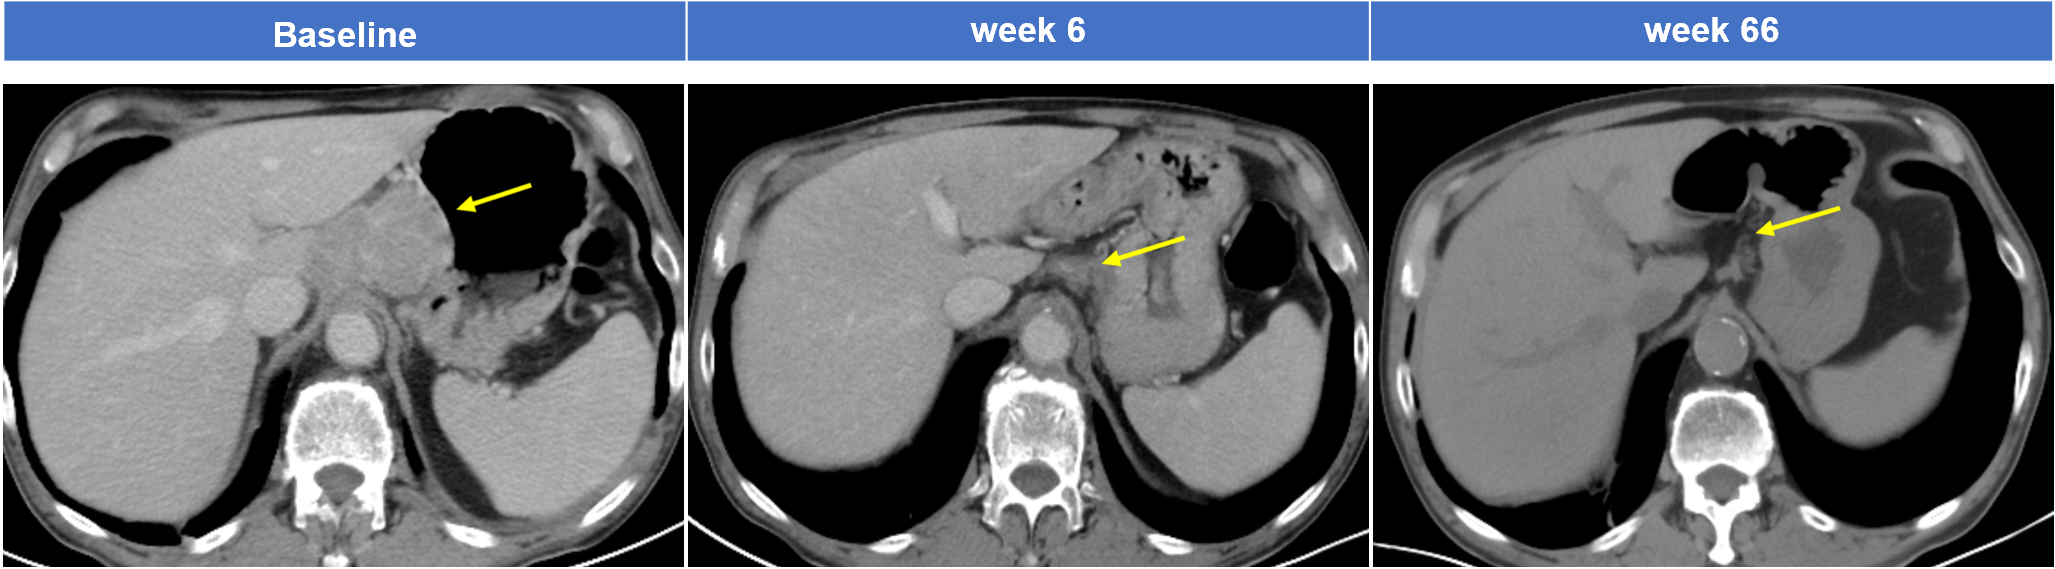

典型案例1